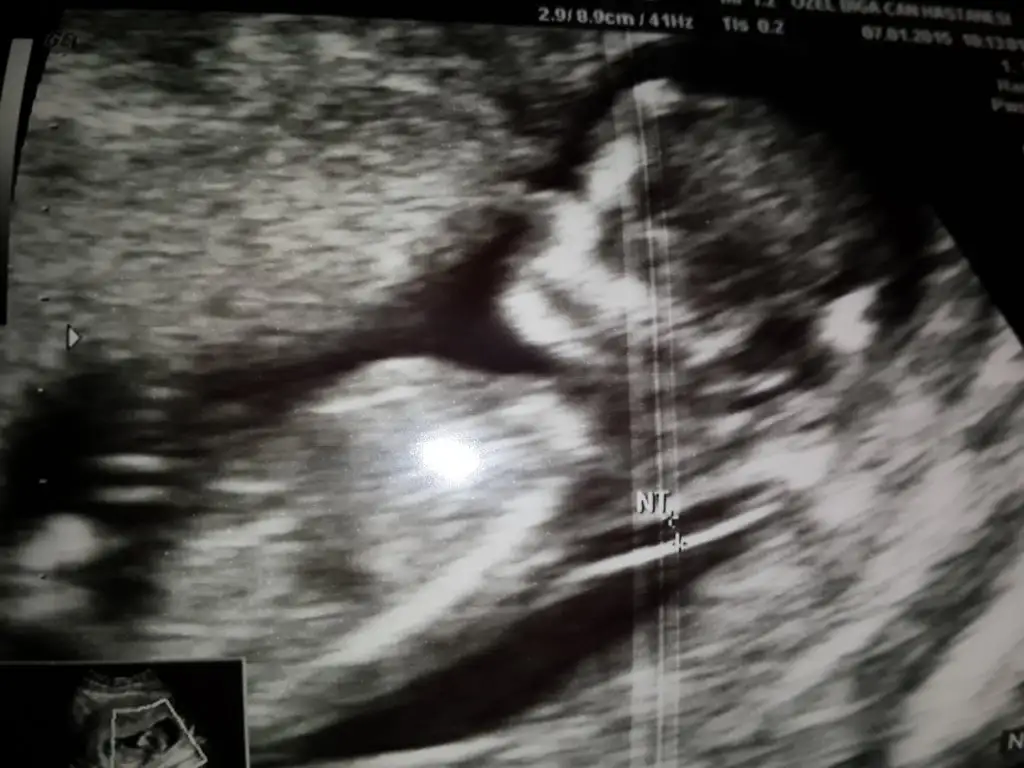

Mehabalar firindan yeni cikmis goruntulerim var:) yorumlarsaniz sevinirim

• IMG-20150107-WA0001.webp

IMG-20150107-WA0001.webp

• Screenshot_2015-01-07-13-17-06.webp

Screenshot_2015-01-07-13-17-06.webp